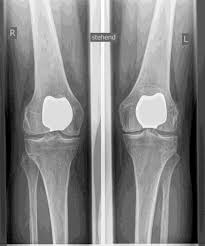

SLIDE PROSTHESIS

Partial knee replacement is possible in all areas of the joint, but is most commonly performed on the inside of the knee joint and is often referred to colloquially as a sled prosthesis. Similar to a full prosthesis, the defective cartilage is replaced with a new surface and a plastic inlay is inserted in between. For a partial prosthesis, all ligament structures, especially the cruciate ligaments, must be largely intact.